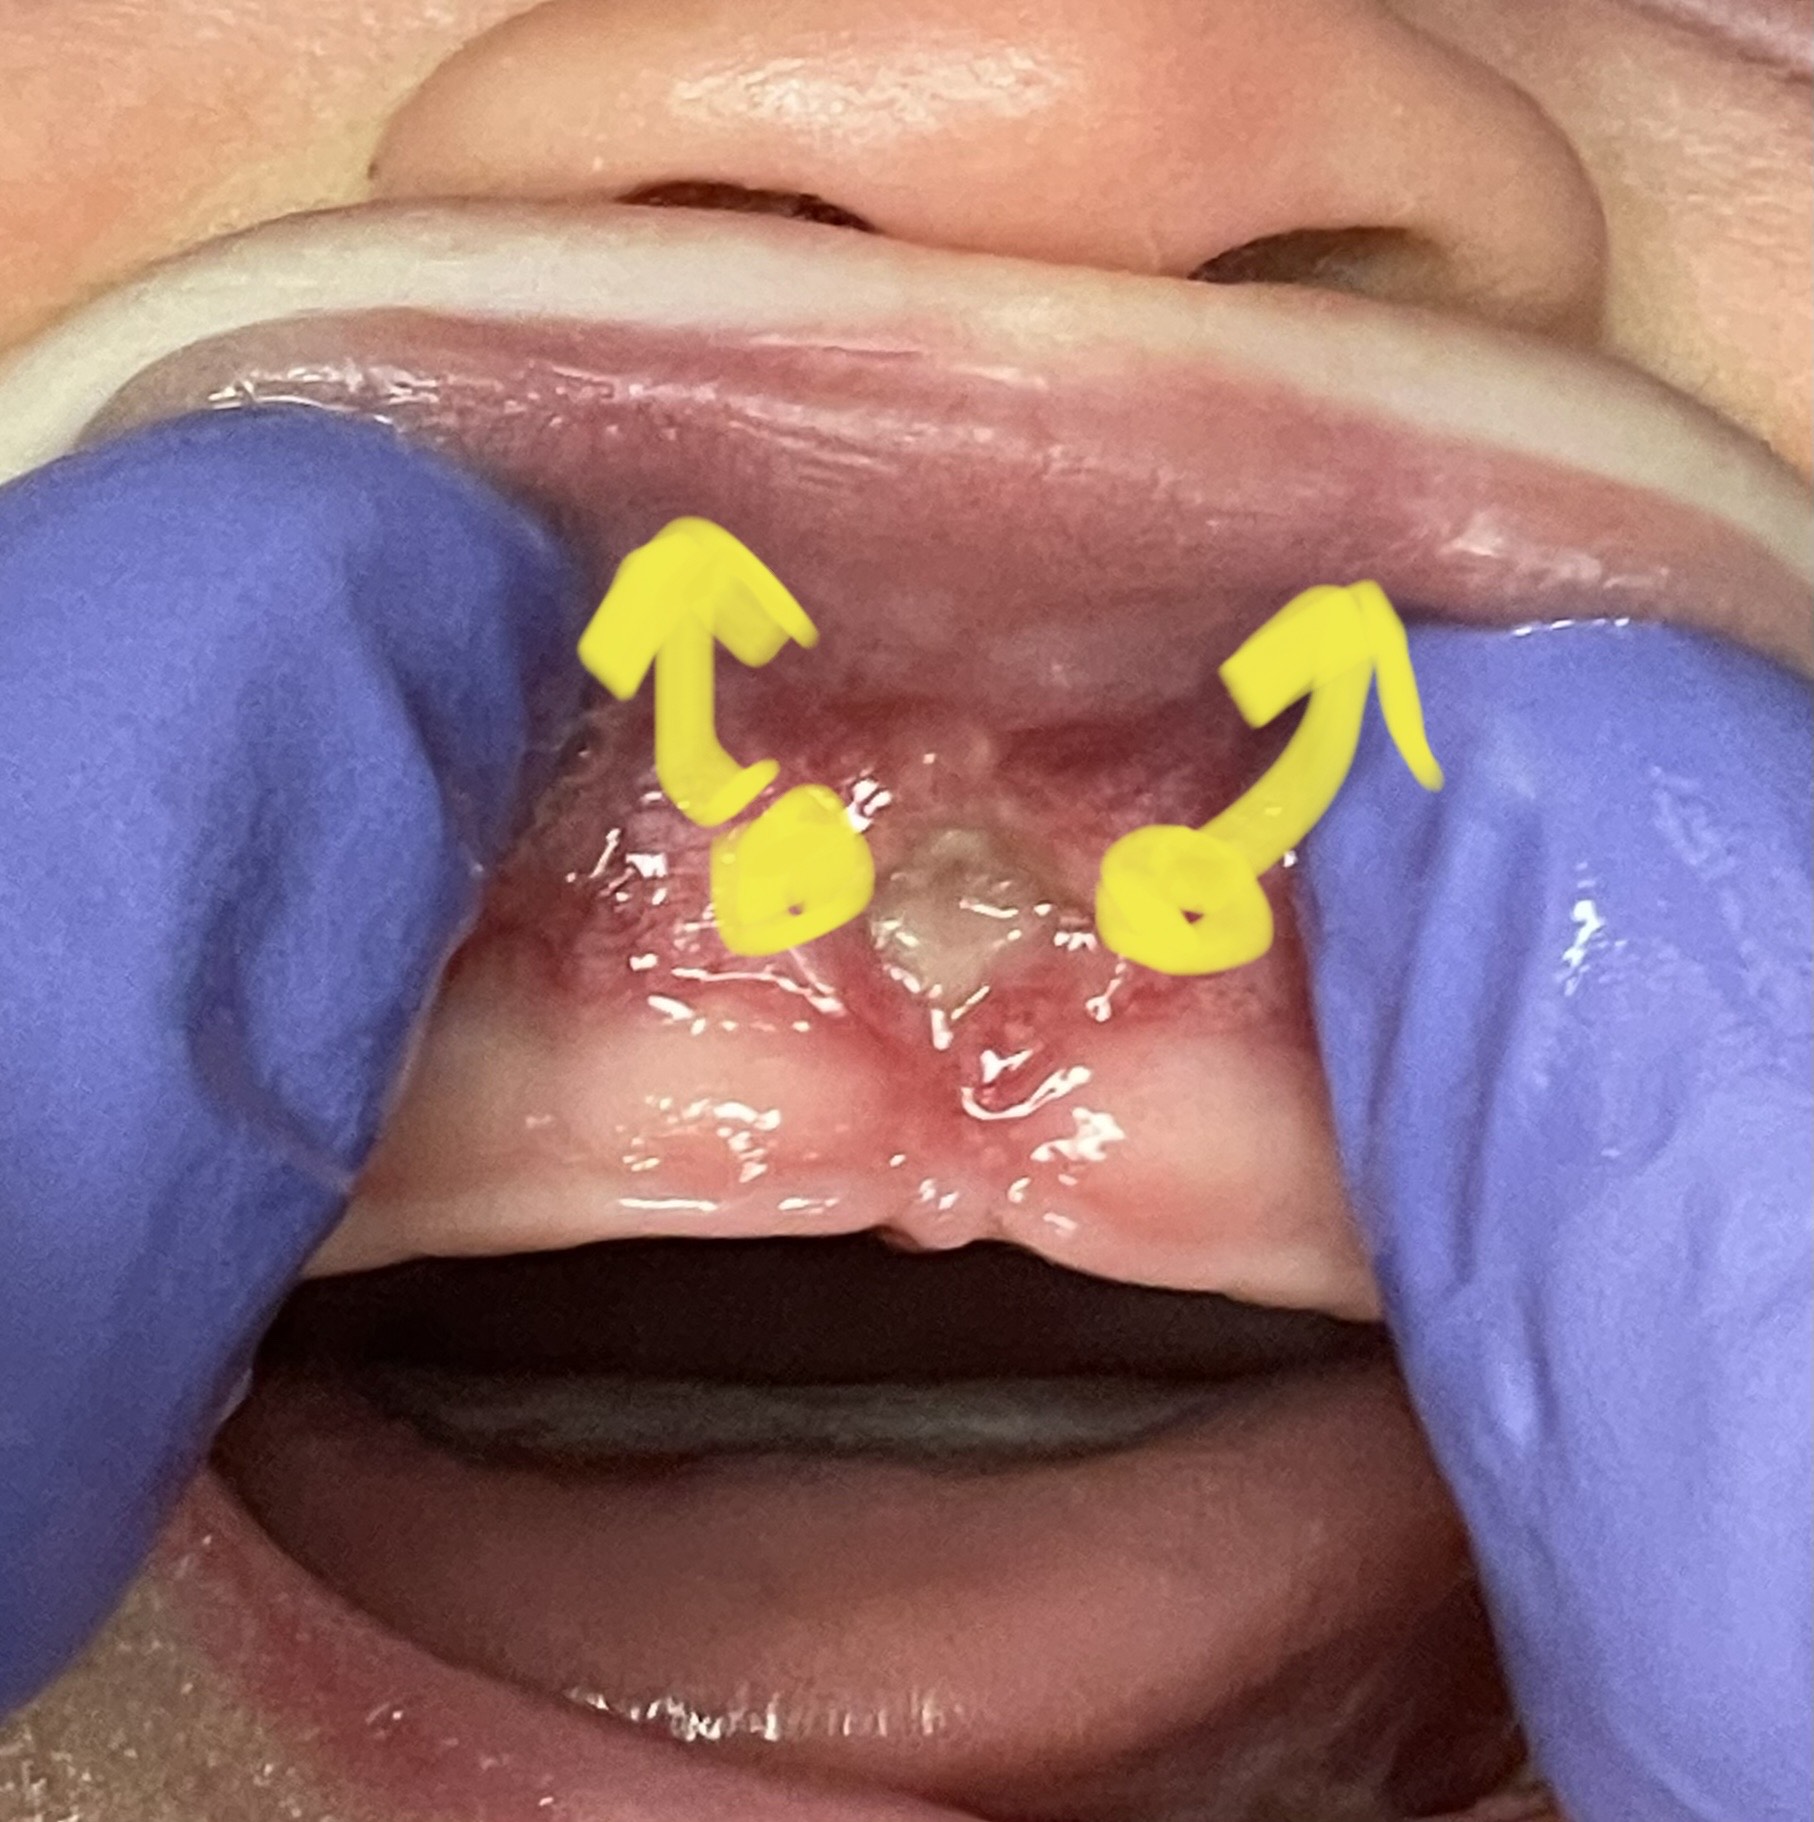

Lip-Tie Release

The goal is for the frenum to heal and re-form as high as possible.

Pull the lip up as high as possible, high enough to press against the nose. You want to see the whole white diamond open up. Press gently but firmly against the wound to massage it and keep the diamond open. Hold for five seconds.

It may bleed slightly when it is stretched, especially if there are longer times between stretches. If you see this, add slightly more pressure, or add one more stretch per day.